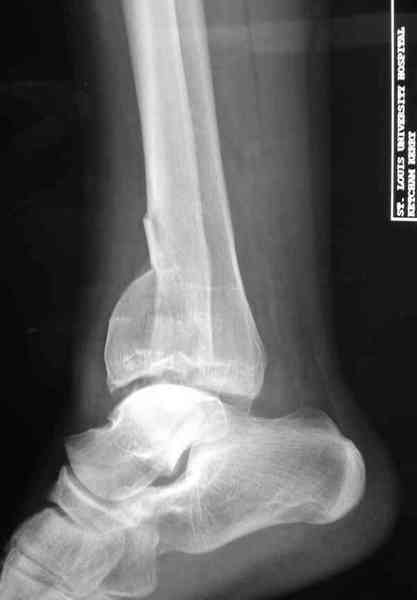

Яков изложил все необходимые аспекты лечения переломов пилона, и, не желая менять тему, решил выставить нашу точку зрения в двух клинических примерах.

При лечении внутрисуставных переломов типа "Pilon"

или "Tibial Plateau" на голени, применение простых

наружных фиксаторов типа "Spanning ExFix" или "Travelling ExFix" стал одним из стандартом этапного лечения.

Дополнительные ренгенограммы после дистракции и

обязательная комьютерная томография дают возможности разузнать топографию расположения фрагментов, что немаловажно для планирования хирургического доступа.

По апексу фрагмента ориентируется при планировании

фиксации, также предоперационно определяется

направление фиксирующего материала: шурупа или спицы с упорной площадкой.

Здесь выставлена пара случаев перелома пилона, оба

случая леченные этапным наружным фиксатором.